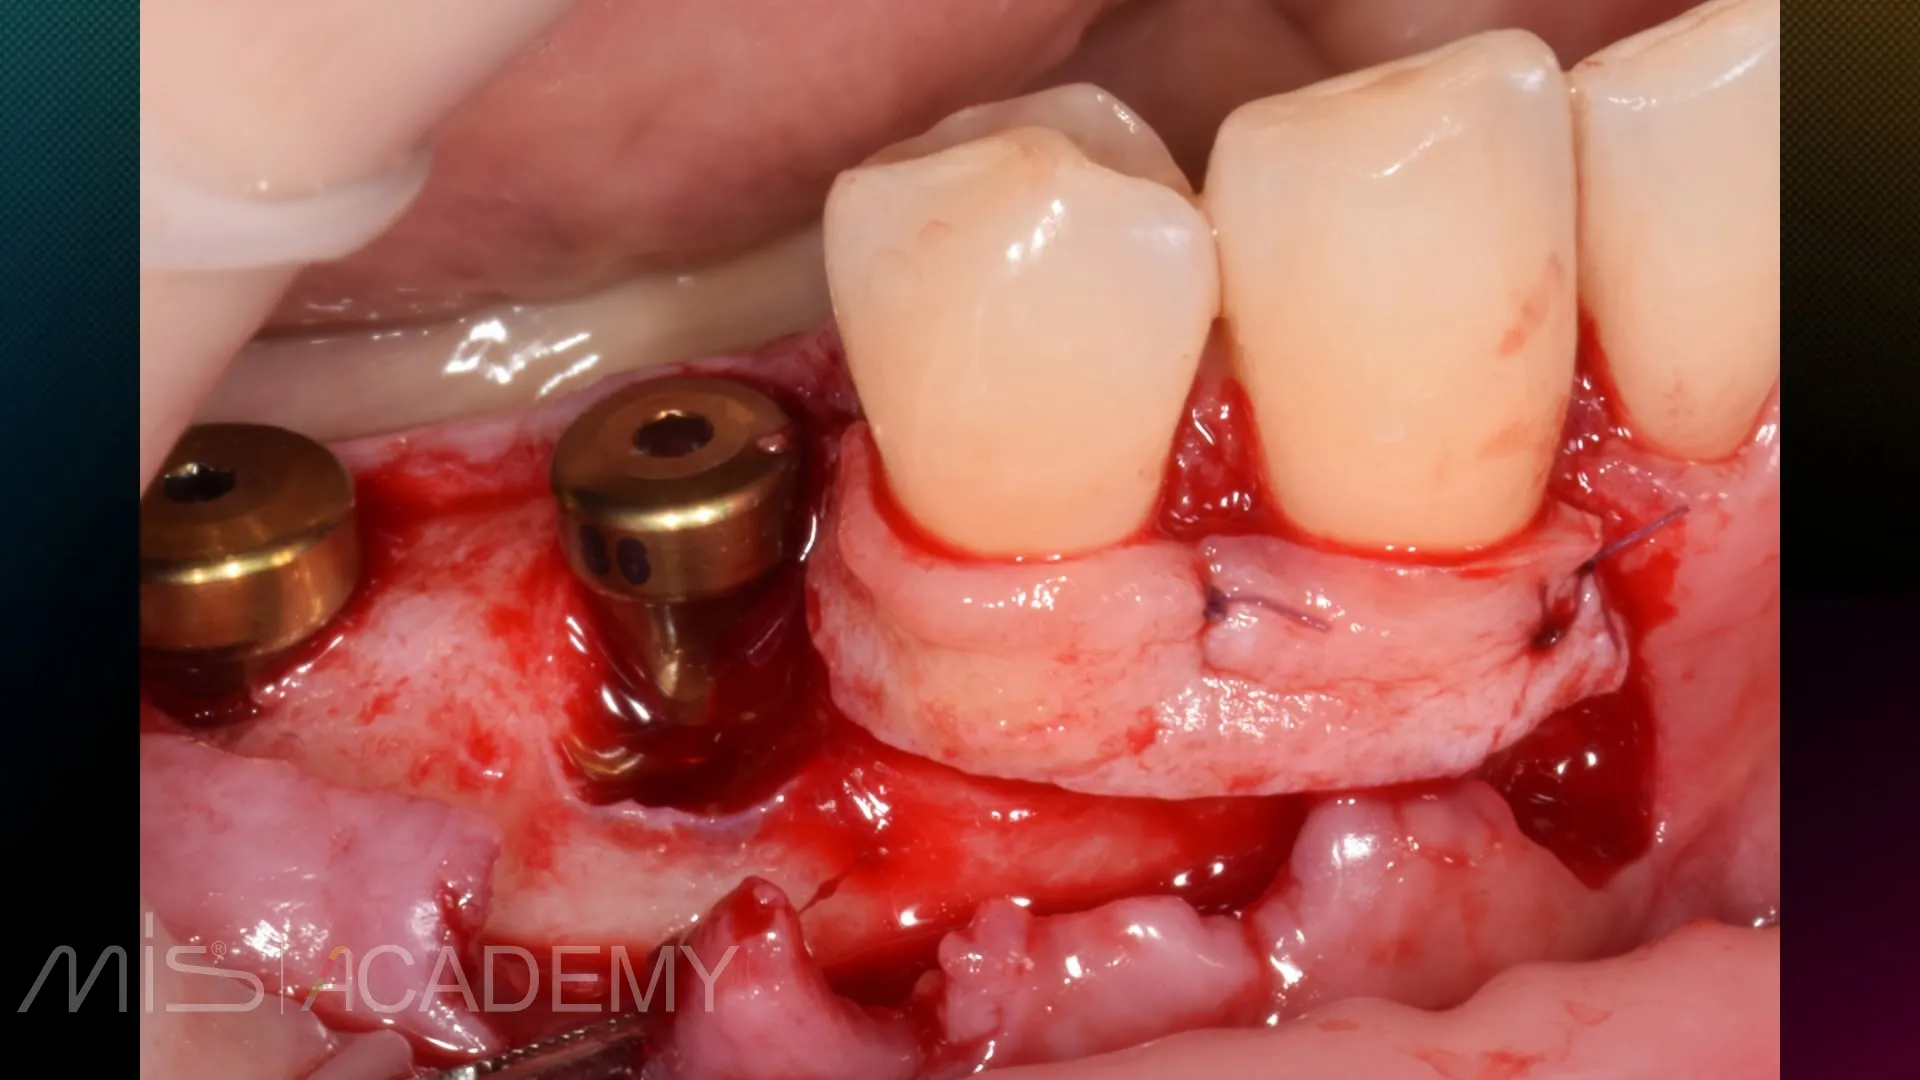

— Установка имплантатов MIS C1 по одномоментному (позиция 4.5 зуба) и отсроченному протоколу (позиция 4.6 зуба).

— Работа с мягкими тканями вокруг имплантатов.